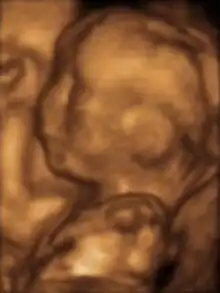

Modern 3D ultrasound images provide greater detail for prenatal diagnosis than the older 2D ultrasound technology.[6] While 3D is popular with parents desiring a prenatal photograph as a keepsake,[7] both 2D and 3D are discouraged by the FDA for non-medical use,[8] but there are no definitive studies linking ultrasound to any adverse medical effects.[9] The following 3D ultrasound images were taken at different stages of pregnancy: